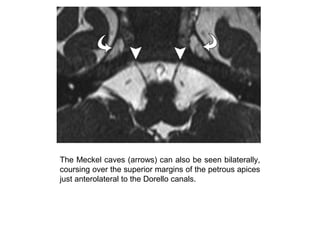

The Meckel caves (arrows) can also be seen bilaterally,

coursing over the superior margins of the petrous apices

just anterolateral to the Dorello canals.